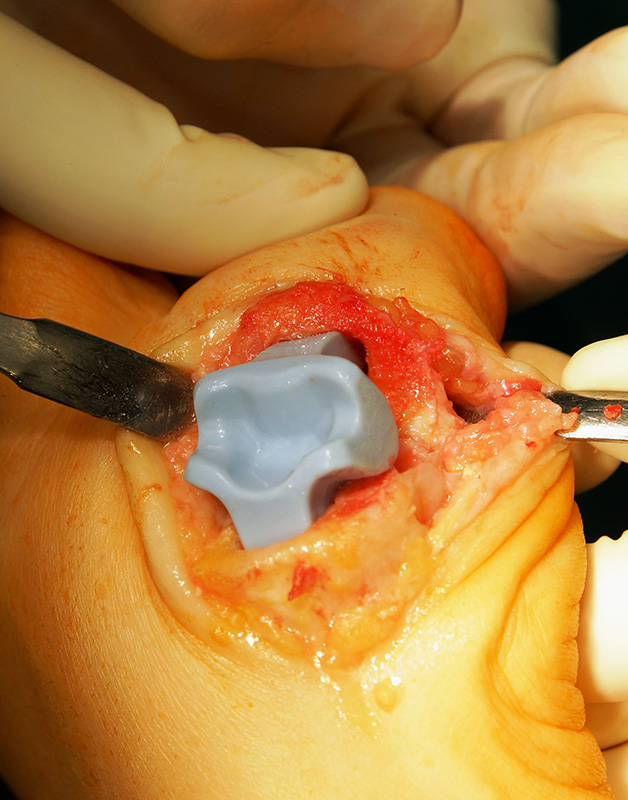

Vor dem Kapselverschluss erfolgt nochmals eine Überprüfung des Bewegungsumfangs. Auch bei maximalem axialem Zug an der Großzehe und bei maximaler Flexion sollte der Spacer nicht luxieren. Eine sorgfältige Kapselnaht dient der Abdeckung des Spacers und der Stabilisierung des Gelenks. Optionale kann eine Redondrainage verwendet werden. Der Hautverschluss erfolgt in klassischer Nahttechnik.

Die Knochenränder sollten abgerundet werden und bei scharfkantigem Knochen die Grommets als Spacerschutz verwendet werden. Die Osteotomie kann zur Optimierung der Beweglichkeit leicht schräg nach dorsal angelegt werden. Die Verwendung der Raspeln mit proximaler und distaler Unterscheidung (Bezeichnung P oder D) reduziert das Risiko der Perforation in das Interphalangeal-Gelenk, da die entsprechenden distalen Raspeln kürzer sind.

Um eine Beschädigung des Spacers zu vermeiden sollten keine scharfen OP Instrumenten während der Implantation zum Einsatz kommen. Scharfe Instrumente können die Oberfläche des Spacers beschädigen. Dies kann zu Rissen der Siliconoberfläche führen, was einen vorzeitigem Spacerbruch begünstigt. Bei Fehlstellungen im Metatarsophalangeal-Gelenk (Hallux valgus/varus und Intermetatarsalwinkel größer 15°) ist die Gefahr der Spacermigration und Luxation erhöht. Ggf. sind hier proximale Korrekturosteotomien und gelegentlich auch ein lateral Release evtl. mit Resektion des lateralen Sesambeins erforderlich. Die Silastik Spacer sind nicht zur Achsenkorrektur geeignet und sollten nur bei balancierten Kapsel-Bandverhältnissen verwendet werden.